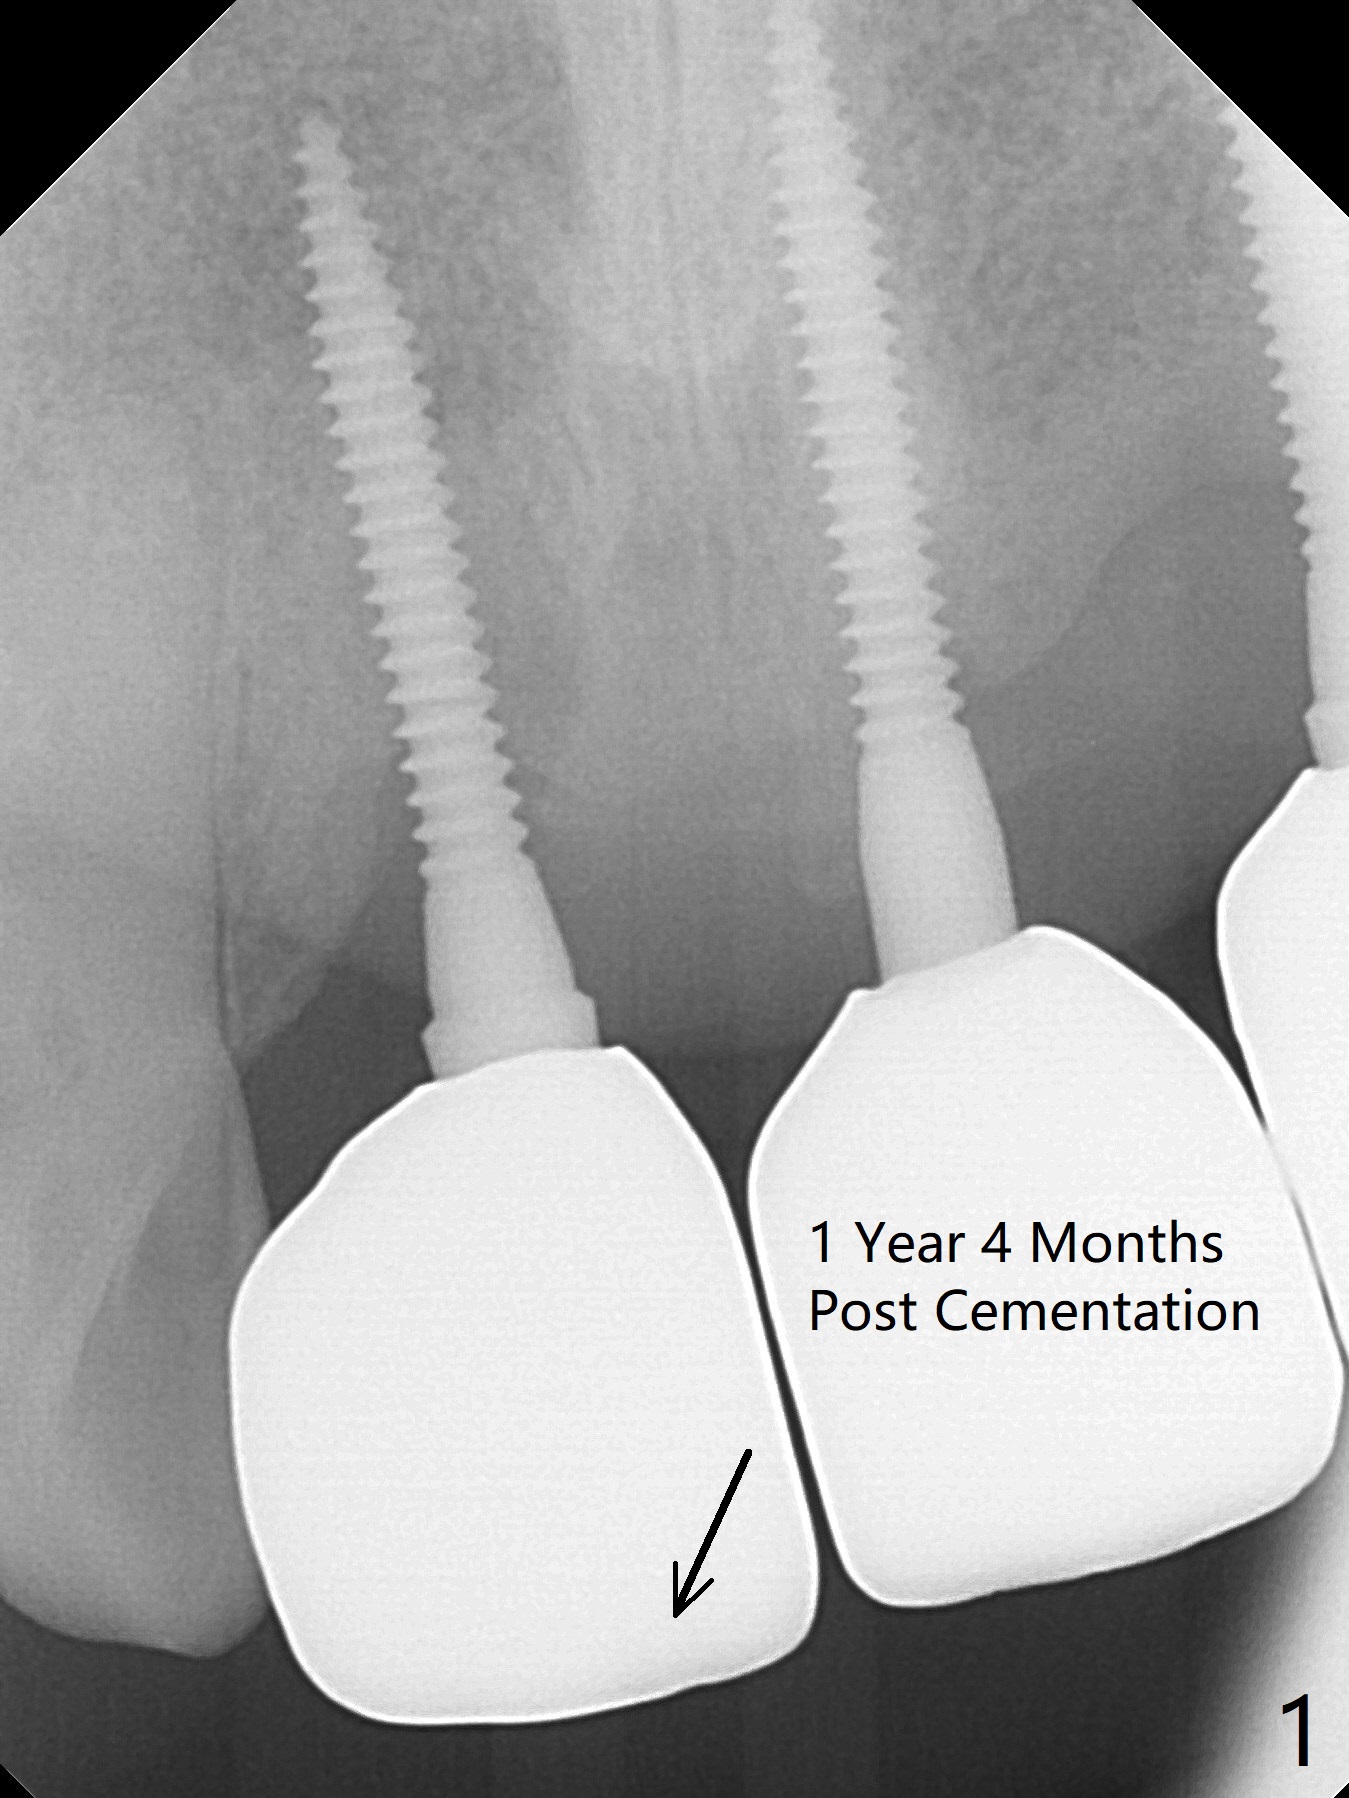

A 43-year-old man has 6 of 1-piece implants in the maxilla (#8-13). His daughter's head hits his upper anterior teeth 7 months post cementation. Exam shows that the tooth #7 has mild percussion. Nine months later the implant crown at #8 becomes displaced and loose when he bites apple (Fig.1 arrow). Forceps are used to remove the crown, leaving a concave implant site (Fig.2). After the crown is bonded to the neighboring tooth/implant crown (Fig.3 *), the patient feels pain from the neighboring tooth. The alveolus is 4.3 mm wide (Fig.4 (2.9 mm preop)), allowing 2.5 or 3.0 mm immediate implant re-placement (Fig.5). A 2.0/3.0 mm trephine bur will be used for implant removal. Try to place the new implant slightly distal to improve the trajectory (Fig.6). Particulate and/or onlay graft is an option. Prepare dummy implants. As planned, the fractured implant is removed by using a 2.0/3.0 mm trephine bur following incision (Fig.7). After use of Lindamann bur to remove the distal bone, a 3x14(4) mm dummy implant is placed with 20 Ncm (Fig.8). A longer implant could be used (3x16(2 or 4) mm), but a 3.5x13 mm 1-piece implant is placed with ~ 50 Ncm after use 3.0 mm drill (Fig.9,10). Allograft is placed around the implant (Fig.9,10 *), followed by Amnion-Chorion membrane and 5-0 PGA sutures (Fig.11). Allograft placed around the implant (Fig.9 *) appears to be able to prevent implant thread exposure 4 months postop (Fig.12). PA is taken when the crown is cemented (Fig.13). Four months postop cementation of #8 crown, the patient returns because of #9 mobility (Fig.14). In fact the implant fractures when the loose crown is removed with forceps; there is bone loss at #10. Bone graft will be placed at #10 with sticky bone (PRFx1), while the implant at #9 is redo. The ridge is wide enough for a 3.5x10 mm implant (Fig.16 (CT taken when #8 implant fractured)). Also prepare Tatum angled 1-piece implant. The 2 mm implant is too thin when occlusion contact at #10-13 is incomplete. The crowns will be redone when the implant at #9 is osteointegrated.